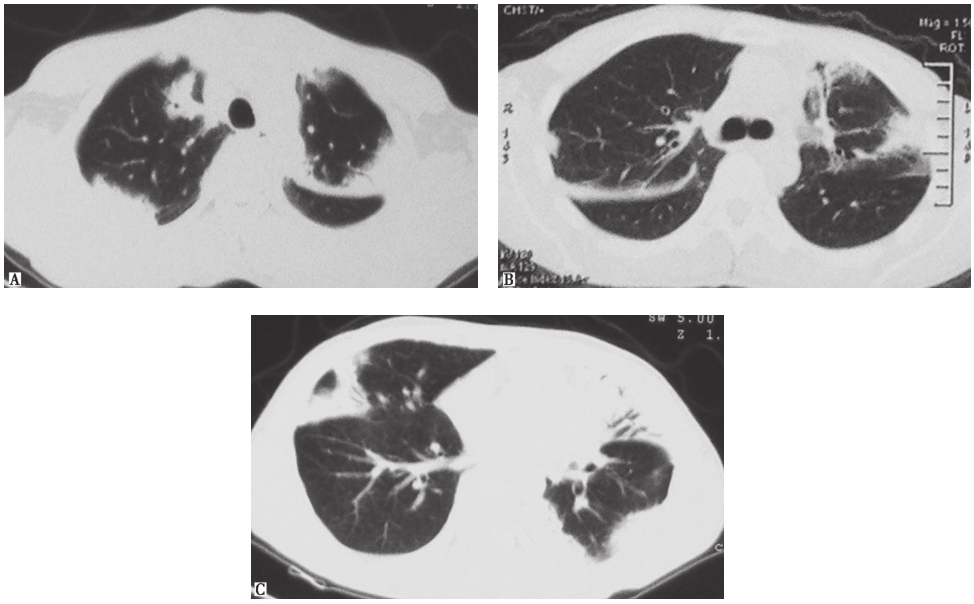

1小时条评论30岁男性,因左侧背痛1个月伴胸痛1周入院。胸部影像学表现为两肺多发斑片状渗出,多发结节伴小空洞形成。是不是感染所致? 一、入院疑诊 (一)病例信息 【病史】 男性患者,30岁,因左侧背痛1个月伴胸痛1周入院。患者于1个月前无明显诱因,出现左侧...

1小时条评论43岁男性,因咳嗽6个月入院治疗。期间自服抗生素、止咳化痰药物后无效。本病例是感染性疾病还是非感染性疾病? 一、入院疑诊 (一)病例信息 【病史】 男性患者,43岁,因咳嗽6个月入院治疗。患者于2009年3月无明显诱因出现咳嗽,间断有少量白痰,无...